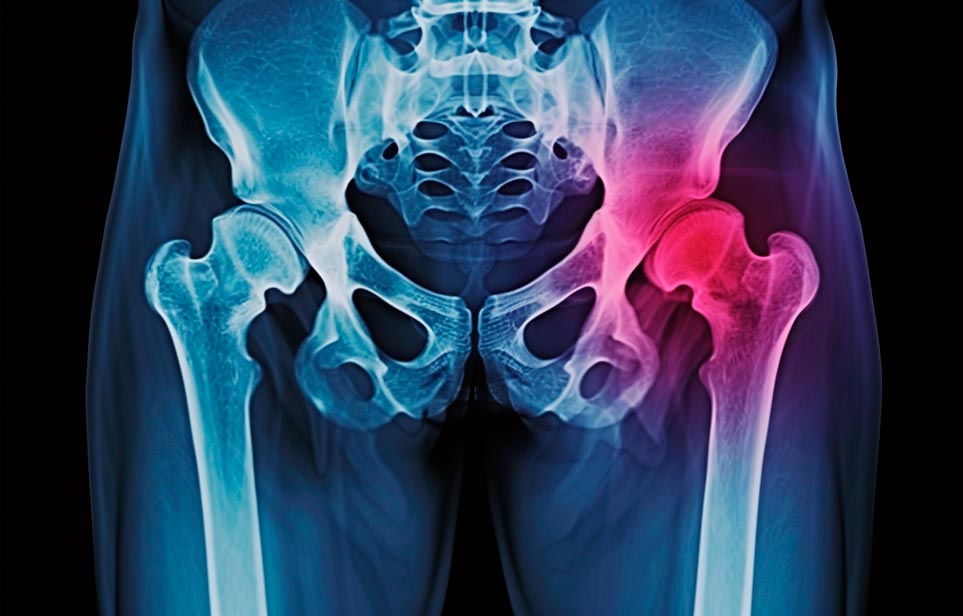

Реабилитация пожилых после перелома шейки бедра в Саках

Такая травма в большей части случаев возникает у граждан преклонного возраста. При её появлении на протяжении длительного времени сохраняются болевые и неприятные ощущения в области паха, при которых серьёзно ухудшается качество жизни, возникает множество последствий для его жизни и здоровья.

По какой симптоматике можно определить перелом шейки бедра?

- Визуально повреждённая нога сокращается на несколько сантиметром из-за сокращения мышц.

- Стопа выворачивается наружу.

- В лежачем положении человек не может поднять ногу.

При такой симптоматике важно незамедлительно обращаться к специалистам для получения всей необходимой помощи, терапии и восстановления после перелома шейки бедра. Если не оказать помощи старику, то это приведёт к гноению, инвалидности, иным видам осложнений.